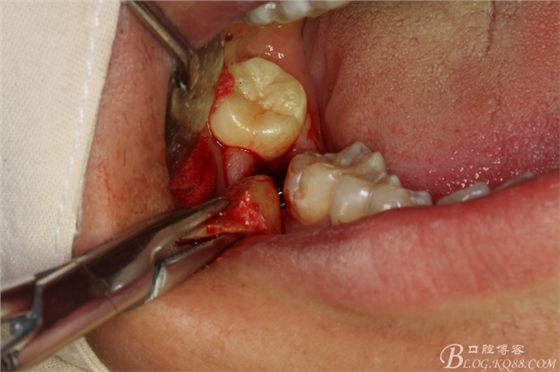

圖10.橫斷牙冠的影像

圖11.牙挺分開(kāi)47牙冠

圖12.挺出47頰側(cè)牙冠

圖13.高速拔牙手機(jī)離斷舌側(cè)牙冠

圖14.挺出47舌側(cè)部分牙冠